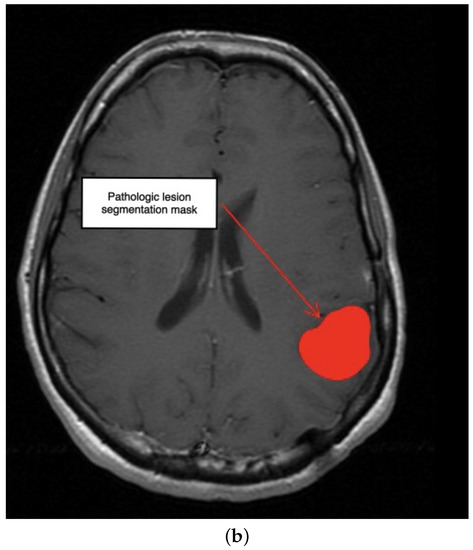

3.1. First Scenario

3.3. Third Scenario